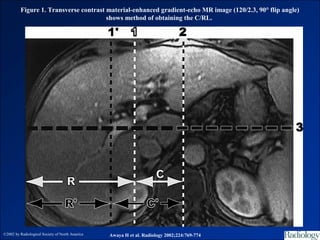

Figure 1. Transverse contrast material-enhanced gradient-echo MR image (120/2.3, 90° flip angle)

shows method of obtaining the C/RL.

©2002 by Radiological Society of North America   Awaya H et al. Radiology 2002;224:769-774

HPT I / Gan trái < 0,35

HPT I / Gan phải > 0,65